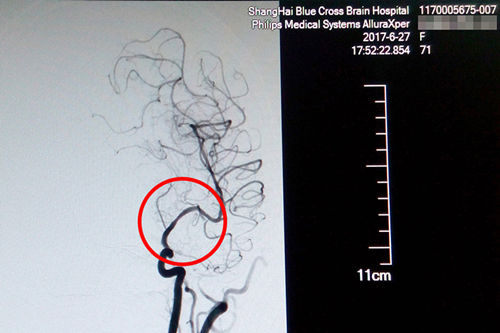

术后DSA影像显示,患者血管狭窄部位血流恢复正常

术后CT影像:支架成功置入

就这样,这台DSA手术又一次获得了成功,术后CT复查无出血,患者恢复情况良好,这才出现了本文开头的感人一幕。原本大面积脑梗、病情凶险的的盛阿姨在李主任和团队的努力下,通过DSA球囊扩张支架置入术,平安度过了生命中的一个转折点。随后,在不到一个月的时间里,她的语言功能已逐渐恢复,四肢肌力已经接近正常水平,目前正在积极接受康复治疗中。